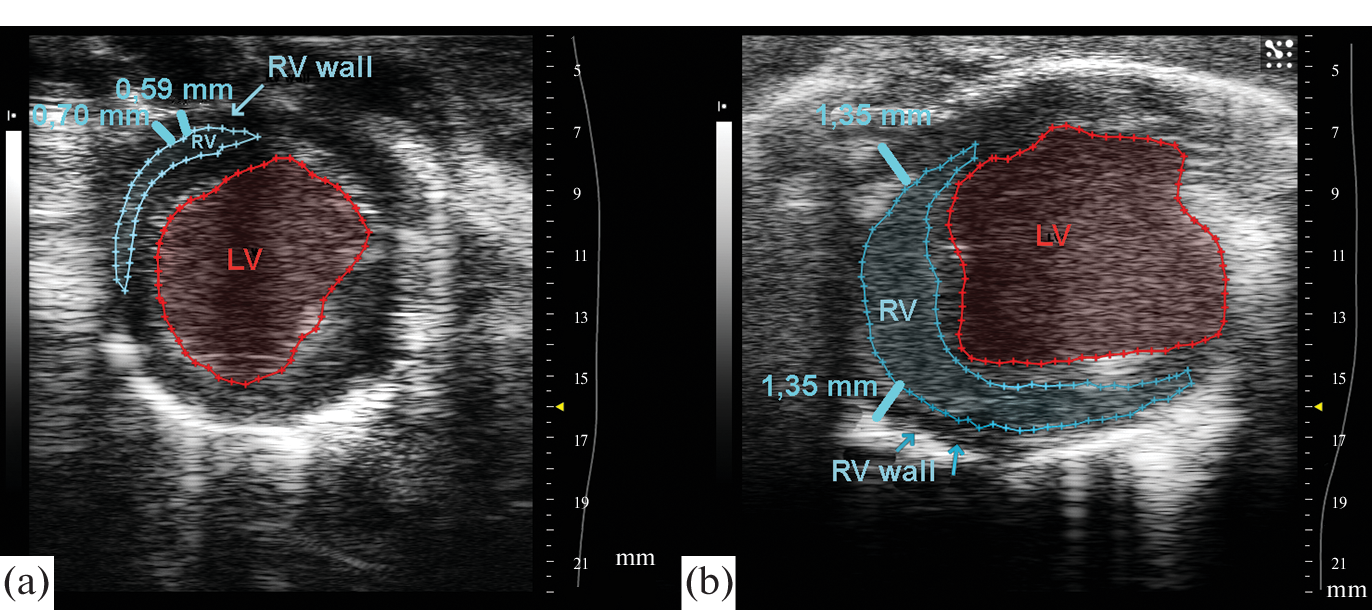

- Spyropoulos F, Vitali SH, Touma M, Rose CD, Petty CR, Levy P, Kourembanas S, Christou H (2020) Echocardiographic markers of pulmonary hemodynamics and right ventricular hypertrophy in rat models of pulmonary hypertension. Pulm Circ 10: 2045894020910976. https://doi.org/10.1177/2045894020910976

- Zhu Z, Godana D, Li A, Rodriguez B, Gu C, Tang H, Minshall RD, Huang W, Chen J (2019) Echocardiographic assessment of right ventricular function in experimental pulmonary hypertension. Pulm Circ 9: 2045894019841987. https://doi.org/10.1177/2045894019841987